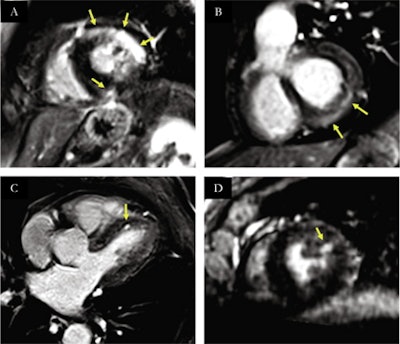

In patients with structural heart disease, all LGE-positive segments on LR-LGE were also detected on HR-LGE (80/391) with 21 additional enhanced segments visible only on HR-LGE (101/391).

Overall, a definite diagnosis using the new sequence was obtained in 15 out of 20 of the COVID-19 patients, including myocarditis in nine, multiple microinfarctions in two, myocardial infarction in two, and takotsubo cardiomyopathy in two.